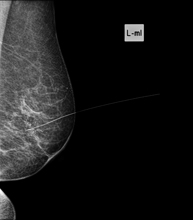

Marcaje prequirúrgico con arpón

Lesiones mamarias de pequeño tamaño, no palpables y tributarias de una cirugía limitada, que necesitan de un marcaje previo a la intervención de la zona a estudio mediante la colocación de un arpón. El arpón es un fino alambre con una angulación en su punta (arpón) que se queda fijo en la zona de la mama que se determina. Bajo control mamográfico o ecográfico, el médico radiólogo introduce el arpón en el interior de la lesión, donde queda fijado. Esto permitirá al cirujano localizar con seguridad la lesión. La duración media es de 20 minutos y presenta ligeras molestias. Habitualmente se realiza escasas horas antes de ir al quirófano, aunque se puede realizar el día anterior.